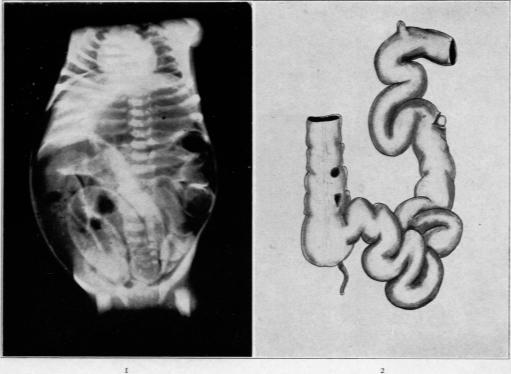

Meconium Ileus with Congenital Stenosis of the Main Pancreatic Duct.

Am J Pathol. 1929 May;5(3):249-262.5.